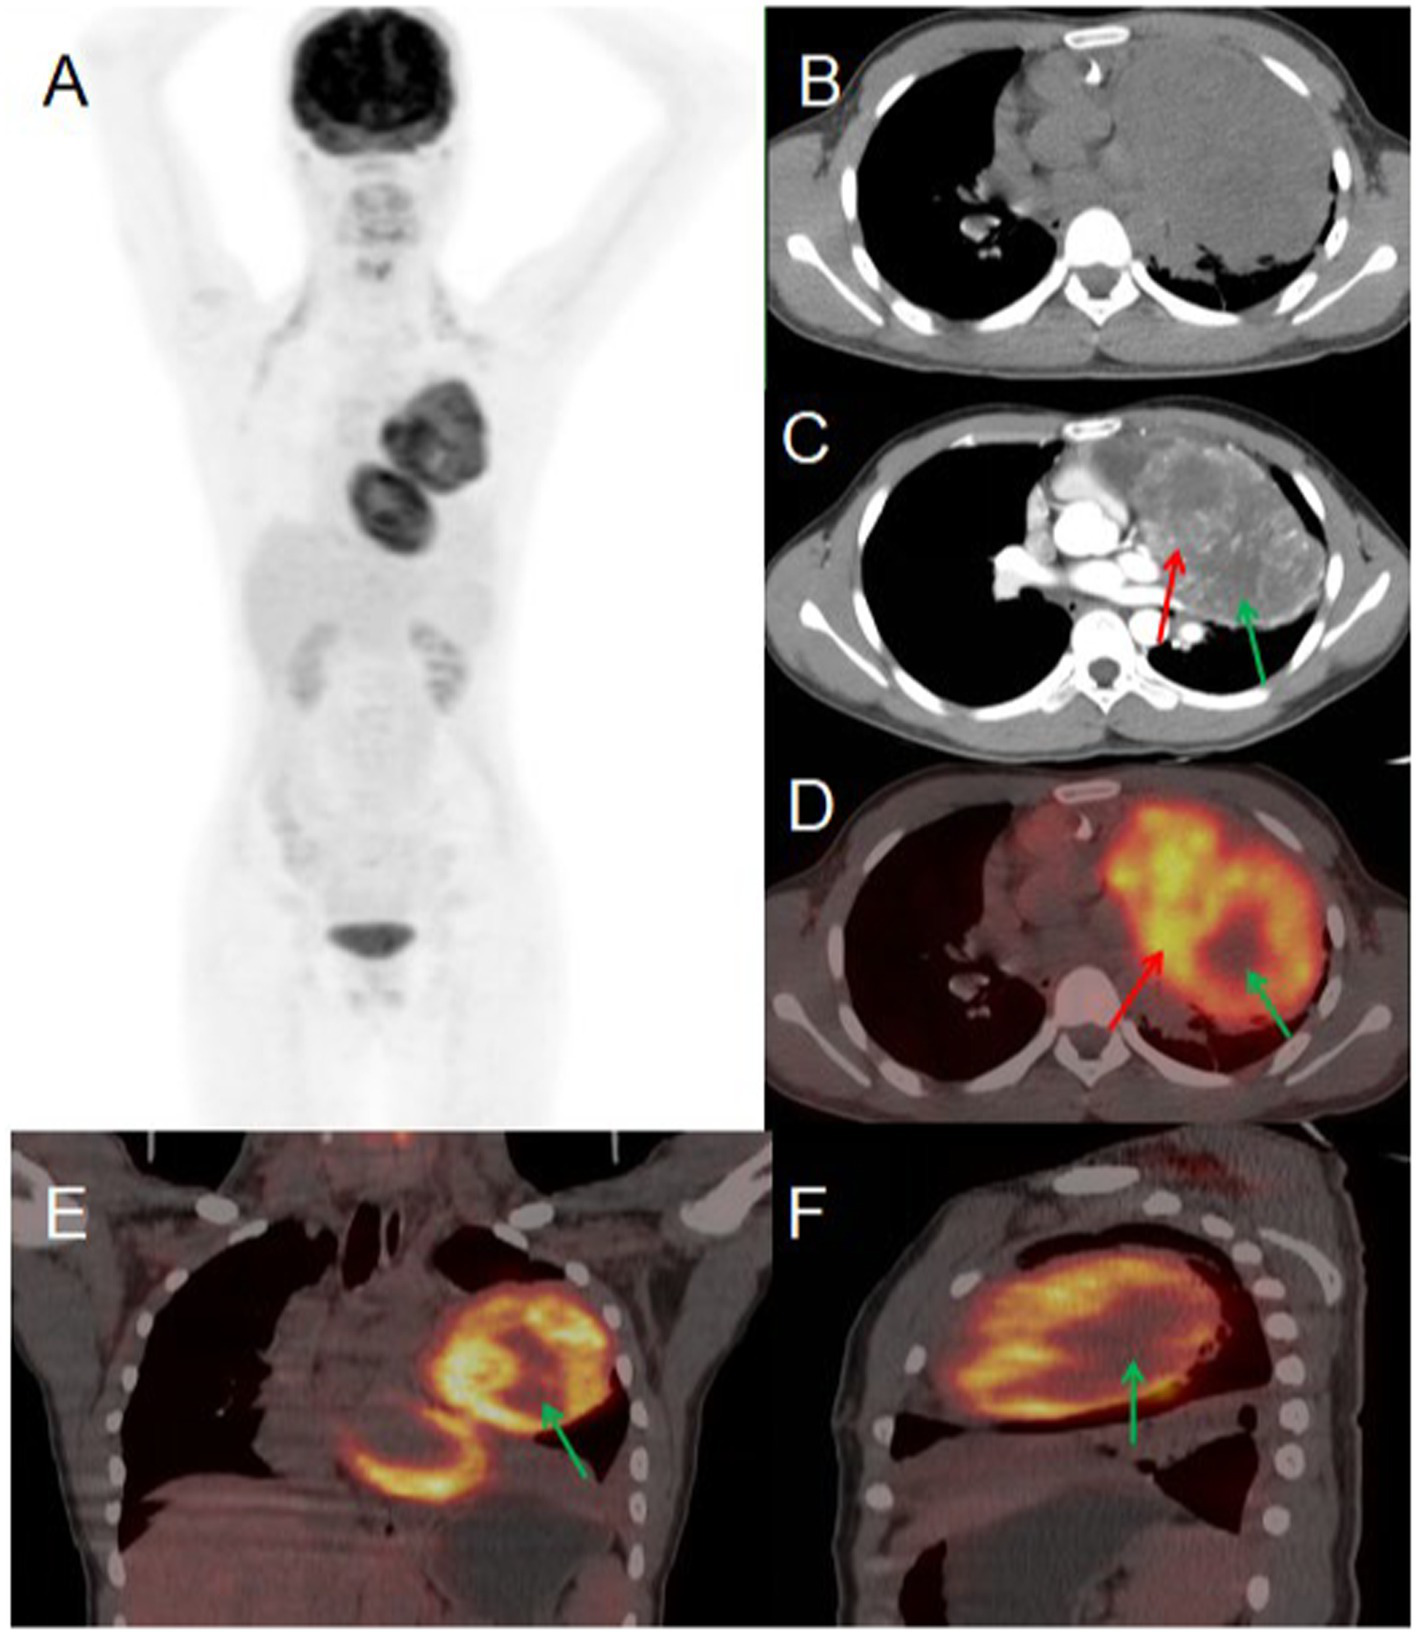

A 56-year-old male presented to Jiangxi Provincial People’s Hospital on January 20, 2023, reporting a 20-day history of spontaneous left-sided chest tightness and pain unrelated to physical exertion. The symptoms had resolved spontaneously prior to presentation. The patient denied associated symptoms including hemoptysis, blood-streaked sputum, fever, night sweats, fatigue, palpitations, additional chest pain, headache, dizziness, nausea, vomiting, diarrhea, or melena. The patient had no history of chronic disease and a history of other types of tumor. He sought further evaluation and treatment at our institution. Tumor marker testing yielded the following results: NSE 19.90 (0–16.3) ng/ml, CF21-1 4.52 (0–3.3 ng/mL), AFP 6.5 (0–7 ng/mL), CEA 3.73 (0–6.5 ng/mL), Ferritin 136.00 (30–400 ng/mL), carbohydrate antigen CA199 2.75 (0–27 U/mL), CA50 0.50 (0–25 IU/mL). Contrast-enhanced CT revealed an approximately 81 × 101 mm soft tissue mass in the left upper lobe containing necrotic and cystic degenerative changes. The lesion demonstrated heterogeneous but marked enhancement, with non-enhancing necrotic and cystic components, findings suggestive of malignancy. PET/CT imaging showed the mass with significantly increased FDG uptake (SUVmax 9.6), supporting the preoperative diagnosis of a malignant lesion. Given the high metabolic activity (indicative of aggressive biological behavior) and absence of distant metastases on PET/CT, the multidisciplinary tumor board recommended surgical resection. Final pathological examination confirmed the diagnosis of a malignant solitary fibrous tumor of the lung (see Figure 3).

Figure 3

Female, 56 years old, malignant primary pulmonary solitary fibrous tumors. (A) Whole body MIP. (B) Axial, non-contrast-enhanced CT. (C) Axial, enhanced CT-arterial phase. (D) Axial fusion. (E) Coronal fusion. (F) Sagittal fusion. Contrast-enhanced CT findings: an approximately 81 × 101 mm soft tissue mass was identified in the left upper lobe, demonstrating: heterogeneous but significant enhancement in the solid components (red arrow, C). Non-enhancing areas corresponding to necrosis and cystic degeneration (green arrow, C). 18F-FDG PET/CT findings: the left upper lobe mass displayed: prominent necrotic-cystic degeneration throughout the lesion. Markedly increased FDG avidity in the solid components (SUVmax 9.6; red arrow, D). Absence of significant FDG uptake in the necrotic-cystic areas (green arrow, D–F).